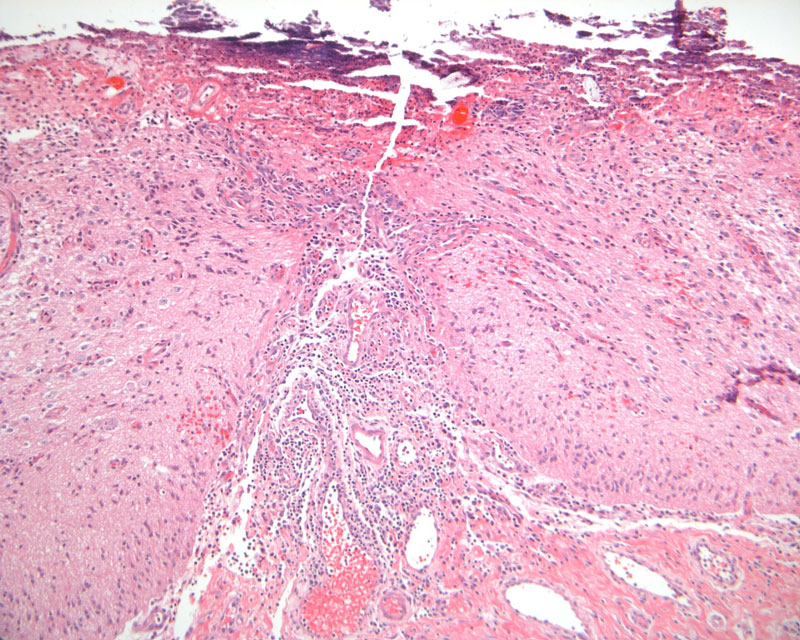

Chronic inflammation: This is a specimen of meningomyelocele without intact covering. Note the chronic inflammatory cell infiltration.

Hematoxylin & eosin